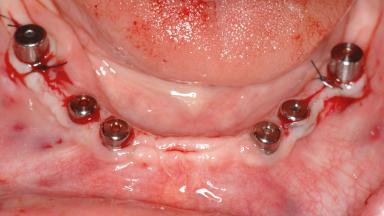

Le Fort I Interpositional Graft and Mandibular Sandwich Osteotomy for Maxillofacial Rehabilitation after Severe Periodontitis

A 47-year-old woman who had suffered from aggressive periodontitis requiring a number of periodontal interventions over more than 10 years was referred by her general dental practitioner and periodontologist for bone augmentation and implant therapy. Her failing dentition had already been scheduled for extraction. The patient expressed a desire for implant-supported fixed restorations and esthetic improvement of her lower face. She had agreed to consult with a maxillofacial surgeon after the referring dentist had suggested bone augmentation. An initial examination by the maxillofacial surgeon revealed mobility of all residual teeth in a patient who was very unhappy with the function of her removable partial dentures. Due to periodontally migrated flaring teeth and loss of occlusal support, the vertical dimension of occlusion was dramatically reduced. The patient was displeased with her lower face because of deepened nasolabial, commissural, and supramental folds.

# of Implants 14

Type of Implants Two-Piece

Bone Augmentation Horizontal|Sinus Floor Elevation|Staged|Vertical

Augmentation Materials Autogenous chips|Autogenous block(s)|Xenogenous|Membrane